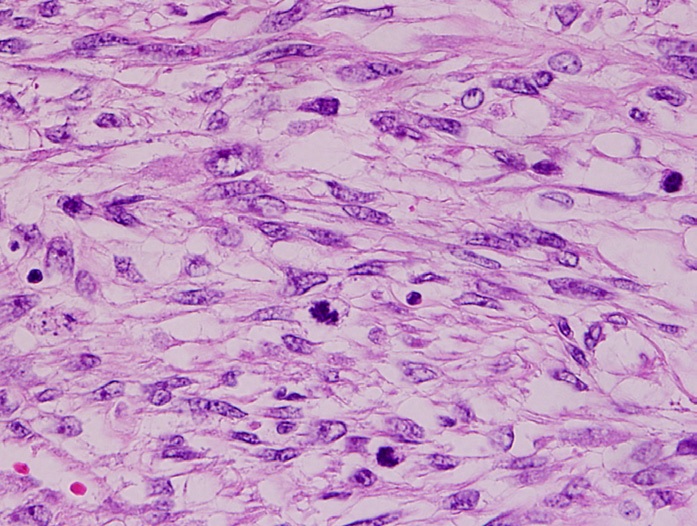

Myxomas typically have a histologic appearance showing an abundance of ground substance and a gelatinous appearance.